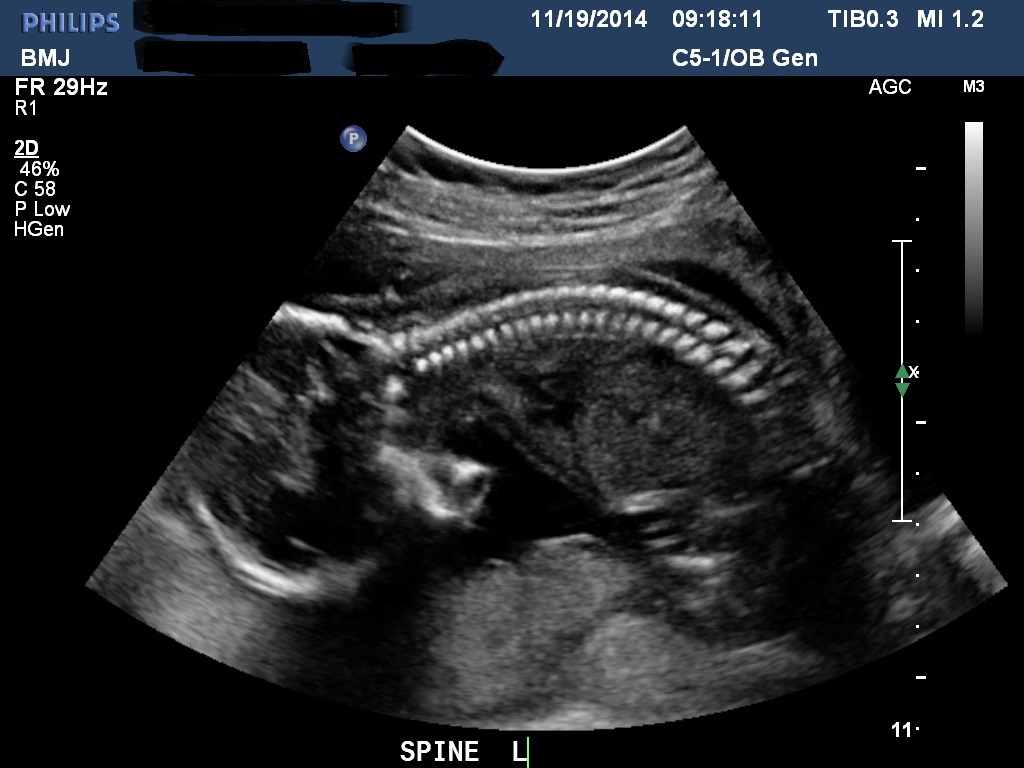

Bumps and U/S pics go here!!!